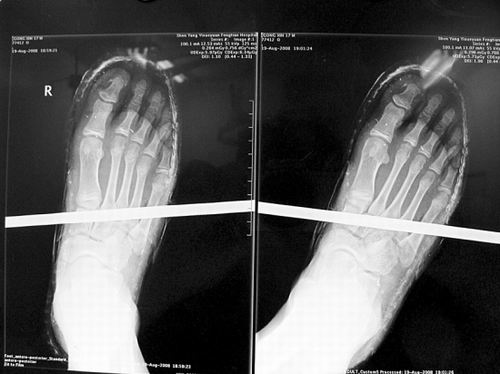

X光片顯示無(wú)大礙

事發(fā)時(shí)男孩穿著一雙布鞋,骨外二科陳賓醫(yī)生操起剪刀,將布鞋一塊塊剪掉。經(jīng)X光透視,醫(yī)生驚奇地發(fā)現(xiàn):男孩雖然被鋼筋穿透了右腳,但骨頭、大的血管和神經(jīng)都沒(méi)受任何傷害!

20日,記者從X光片子上看到,鋼筋避開(kāi)了男孩腳掌骨頭密集的部位,而是從腳弓處穿過(guò),這個(gè)部位基本上以軟組織為主!罢鏇](méi)想到,太神奇了!”幾名醫(yī)生連聲感嘆,術(shù)中,他們分工合作,小心翼翼地將鋼筋取出,并做了引流、清創(chuàng)、包扎。